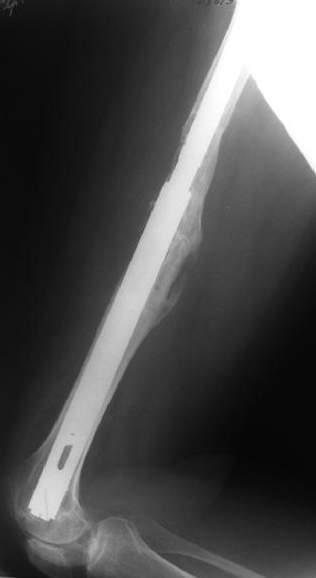

Female, rheumatoid, THA in 2003, car accident in 2006, failed plating. Nailing in Oct 2007. The nail is solid with hollow proximal part where the stem is docked. Last images are in 1 year after

nailing.

Спасибо за обсуждение. После нескольких дней тракции аппаратом сделали. Попытка закрытой репозиции не удалась из-за смещения по ширине, мешали фрагменты цемента. После их удаления репозиция получилась. Еще убрали немного цемента с ножки по латерльной стороне, чтобы обнажить 40-50 мм ее дистальной части, для плотной посадки гвоздя. Дальнейшее введение гвоздя было несложным. Протез показался нам стабильным в проксимальной части как латерально, так и медиально. Картинки в приложении.

THX for the discussion. After few days of traction by ex-fix the surgery was performed. An attempt of closed nailing was unsuccesful because of fragment translation, which was blocked by cement fragments. After removal of broken cement pieces reduction was reached "automagically". Also some cement from lateral part was removed by

chisel to expose distal 40-50 mm of the stem to allow tight fit of the nail. Further fixation by the nail was pretty easy and straightforward. Images attached. The stem looked stable in its proximal part both laterally and medially. Comments/critics are welcome.